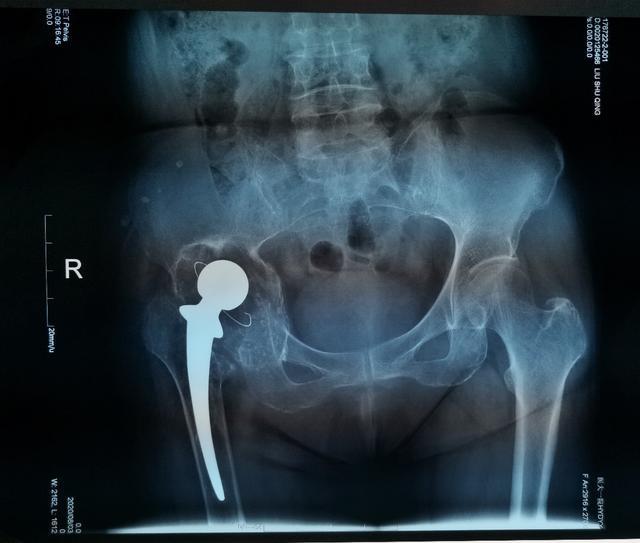

對于復(fù)雜髖關(guān)節(jié)翻修多為高齡患者,由于骨缺損巨大、骨質(zhì)疏松等因素,存在手術(shù)難度大、手術(shù)費用高等難題。近日,哈醫(yī)大一院骨科一病房3D打印團隊,應(yīng)用3D打印技術(shù),通過術(shù)前打印骨骼模型進行模擬假體安裝,成功為一名70歲,全髖關(guān)節(jié)置換術(shù)后15年,髖臼骨缺損巨大,髖臼上部坐骨、髂骨存在巨大空洞型缺損的患者實施了我省首例金屬3D打印三翼髖臼假體(Triflange)+股骨柄假體髖關(guān)節(jié)翻修術(shù),為患者更換了一個新的、穩(wěn)定的髖關(guān)節(jié)。目前患者已康復(fù)出院。

70歲的劉阿姨十五年前因股骨頭壞死進行了全髖關(guān)節(jié)置換手術(shù)。五年前右腿開始有明顯的縮短,髖部疼痛也逐漸加重,來到哈醫(yī)大一院時已經(jīng)無法行走。經(jīng)影像檢查,患者十五年前采用水泥固定髖臼杯,金屬頭和聚乙烯髖臼杯十?dāng)?shù)年的摩擦產(chǎn)生的聚乙烯碎屑已經(jīng)導(dǎo)致髖臼巨大的骨缺損,假體上移,不僅髖臼,甚至坐骨,髂骨都有骨溶解,屬于Paprosky·3B型髖臼側(cè)骨缺損。此類疾病的治療主要采用三翼髖臼假體(Triflange)。由于患者髖臼骨缺損巨大,特別是在髖臼上部存在巨大的空洞型缺損,傳統(tǒng)的Triflange假體不能滿足劉阿姨髖臼的穩(wěn)定支撐和重建,且患者骨質(zhì)疏松,傳統(tǒng)假體骨長入能力難以滿足要求。

為了確保手術(shù)順利,手術(shù)前,耿碩教授根據(jù)患者的影像數(shù)據(jù),經(jīng)過三維重建,真實復(fù)原了患者的右髖關(guān)節(jié)和盆骨模型。借助這一模型,耿碩教授可以全面精準(zhǔn)地了解患者的關(guān)節(jié)結(jié)構(gòu),骨質(zhì)情況等重要信息,為術(shù)前制訂精確地手術(shù)方案提供了重要的依據(jù)。手術(shù)當(dāng)日,耿碩教授手術(shù)團隊按照術(shù)前模擬,順利的將金屬假體精準(zhǔn)地安放在髖關(guān)節(jié)內(nèi)。經(jīng)過一周的康復(fù),患者已順利下地行走并康復(fù)出院。